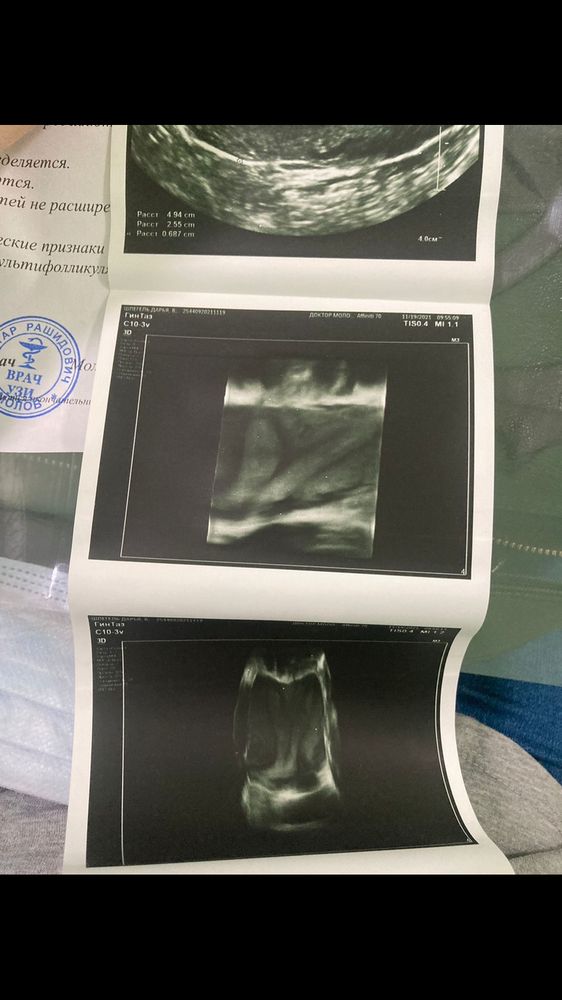

У меня двурогая матка. Два года назад делала МРТ (заключение: МР признаки двурогой матки с удвоенной шейкой. Полость матки не расширена. Зональное строение стенок матки сохранено. Стенки матки не утолщены). На фото - УЗИ (не МРТ). Пытаюсь понять, это полная двурогость или что… про перегородку ничего не пишут, и я так и не понимаю - есть она или нет… но раз две шейки, значит, что-то их разделяет..